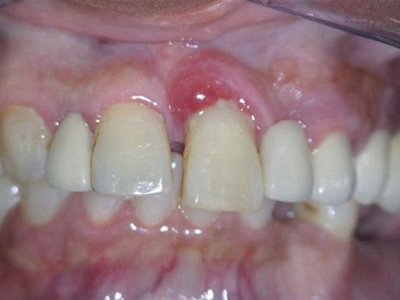

牙龈炎可先引起牙齿与牙龈之间的沟(龈沟)加深,然后牙龈充血,炎症围绕一个或多个牙齿,伴牙龈乳头肿胀和易出血。一般无痛,可自行消退,也可维持轻度炎症数年。

牙龈炎是发生于牙龈组织的炎症,患者可出现牙龈出血伴肿胀、发红、正常形态改变和偶尔不适等症状。本病主要由口腔卫生状况差导致,包括口腔不洁、牙菌斑等,诊断依据临床检查,治疗包括专业牙齿清洁和加强家庭口腔卫生。